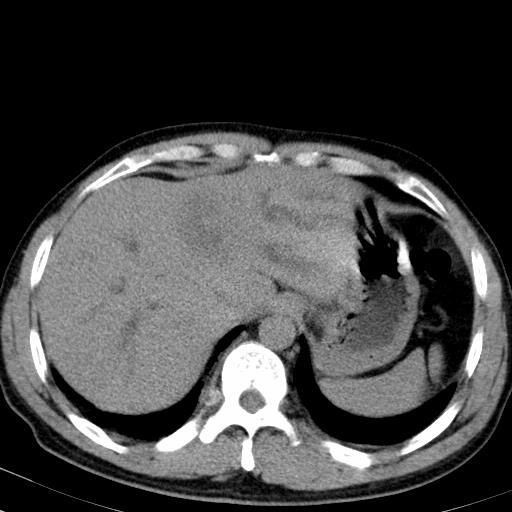

患者上腹部疼痛一月余,伴巩膜黄染;

实事求是的说,强化效果很一般,重点部位应重点观察,但有一点可以明确:肝门部胆管细胞癌。

考虑肝左叶胆管细胞癌侵犯肝门区并肝内胆管及肝总管扩张。

肝左叶肿块清度增强,所在的叶胆管扩张。考虑胆管细胞癌。